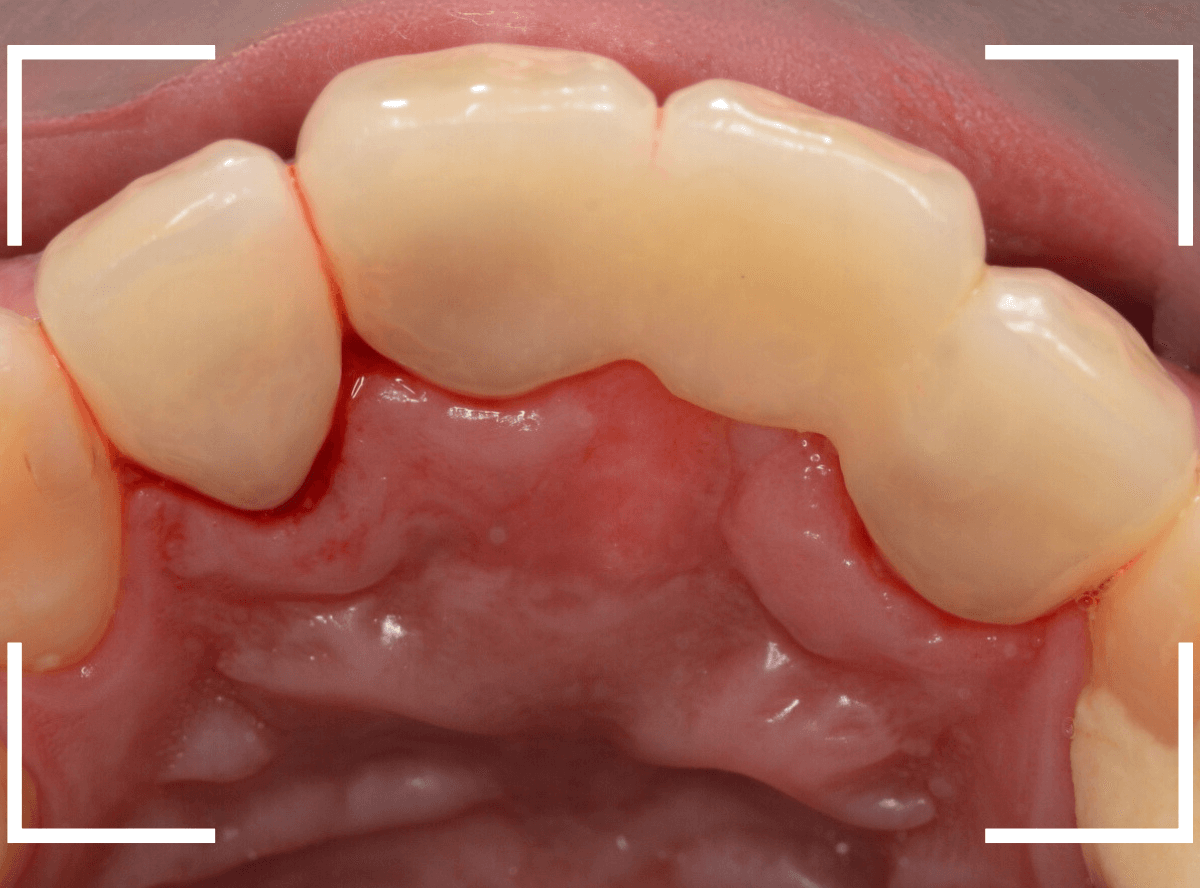

今回は、上の前歯を抜歯した後に放置してしまったので、そろそろ綺麗に作り直したいという患者さんです。

インプラント治療もご提案したのですが、セラミックのブリッジ治療をご希望されました。

ブリッジ治療をする隣の歯も神経処置をした後の虫歯になっていますので、4本同時に治療する事になりました。

まずは虫歯のある歯の治療とファイバーコアのsetを行い、支えとなる歯(支台歯)の形を整えます。

微調整をして、最終setしたところです。

患者さんにも満足していただけたようで、ホッとしました。

治療前後の比較です。

治療はさし歯を入れて終わりではありません、末永く使うために、定期メンテナンスにも忘れずに来ていただくよう、お話しました。